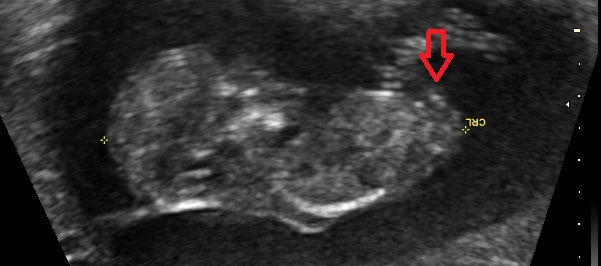

I was 11w5d when I had the scan, although I was measuring 12w1d. I know it's still pretty early, but am wondering if you see anything on these (terrible quality) scan pics! Attachment 23572Attachment 23571Attachment 23573Attachment 23574Attachment 23575